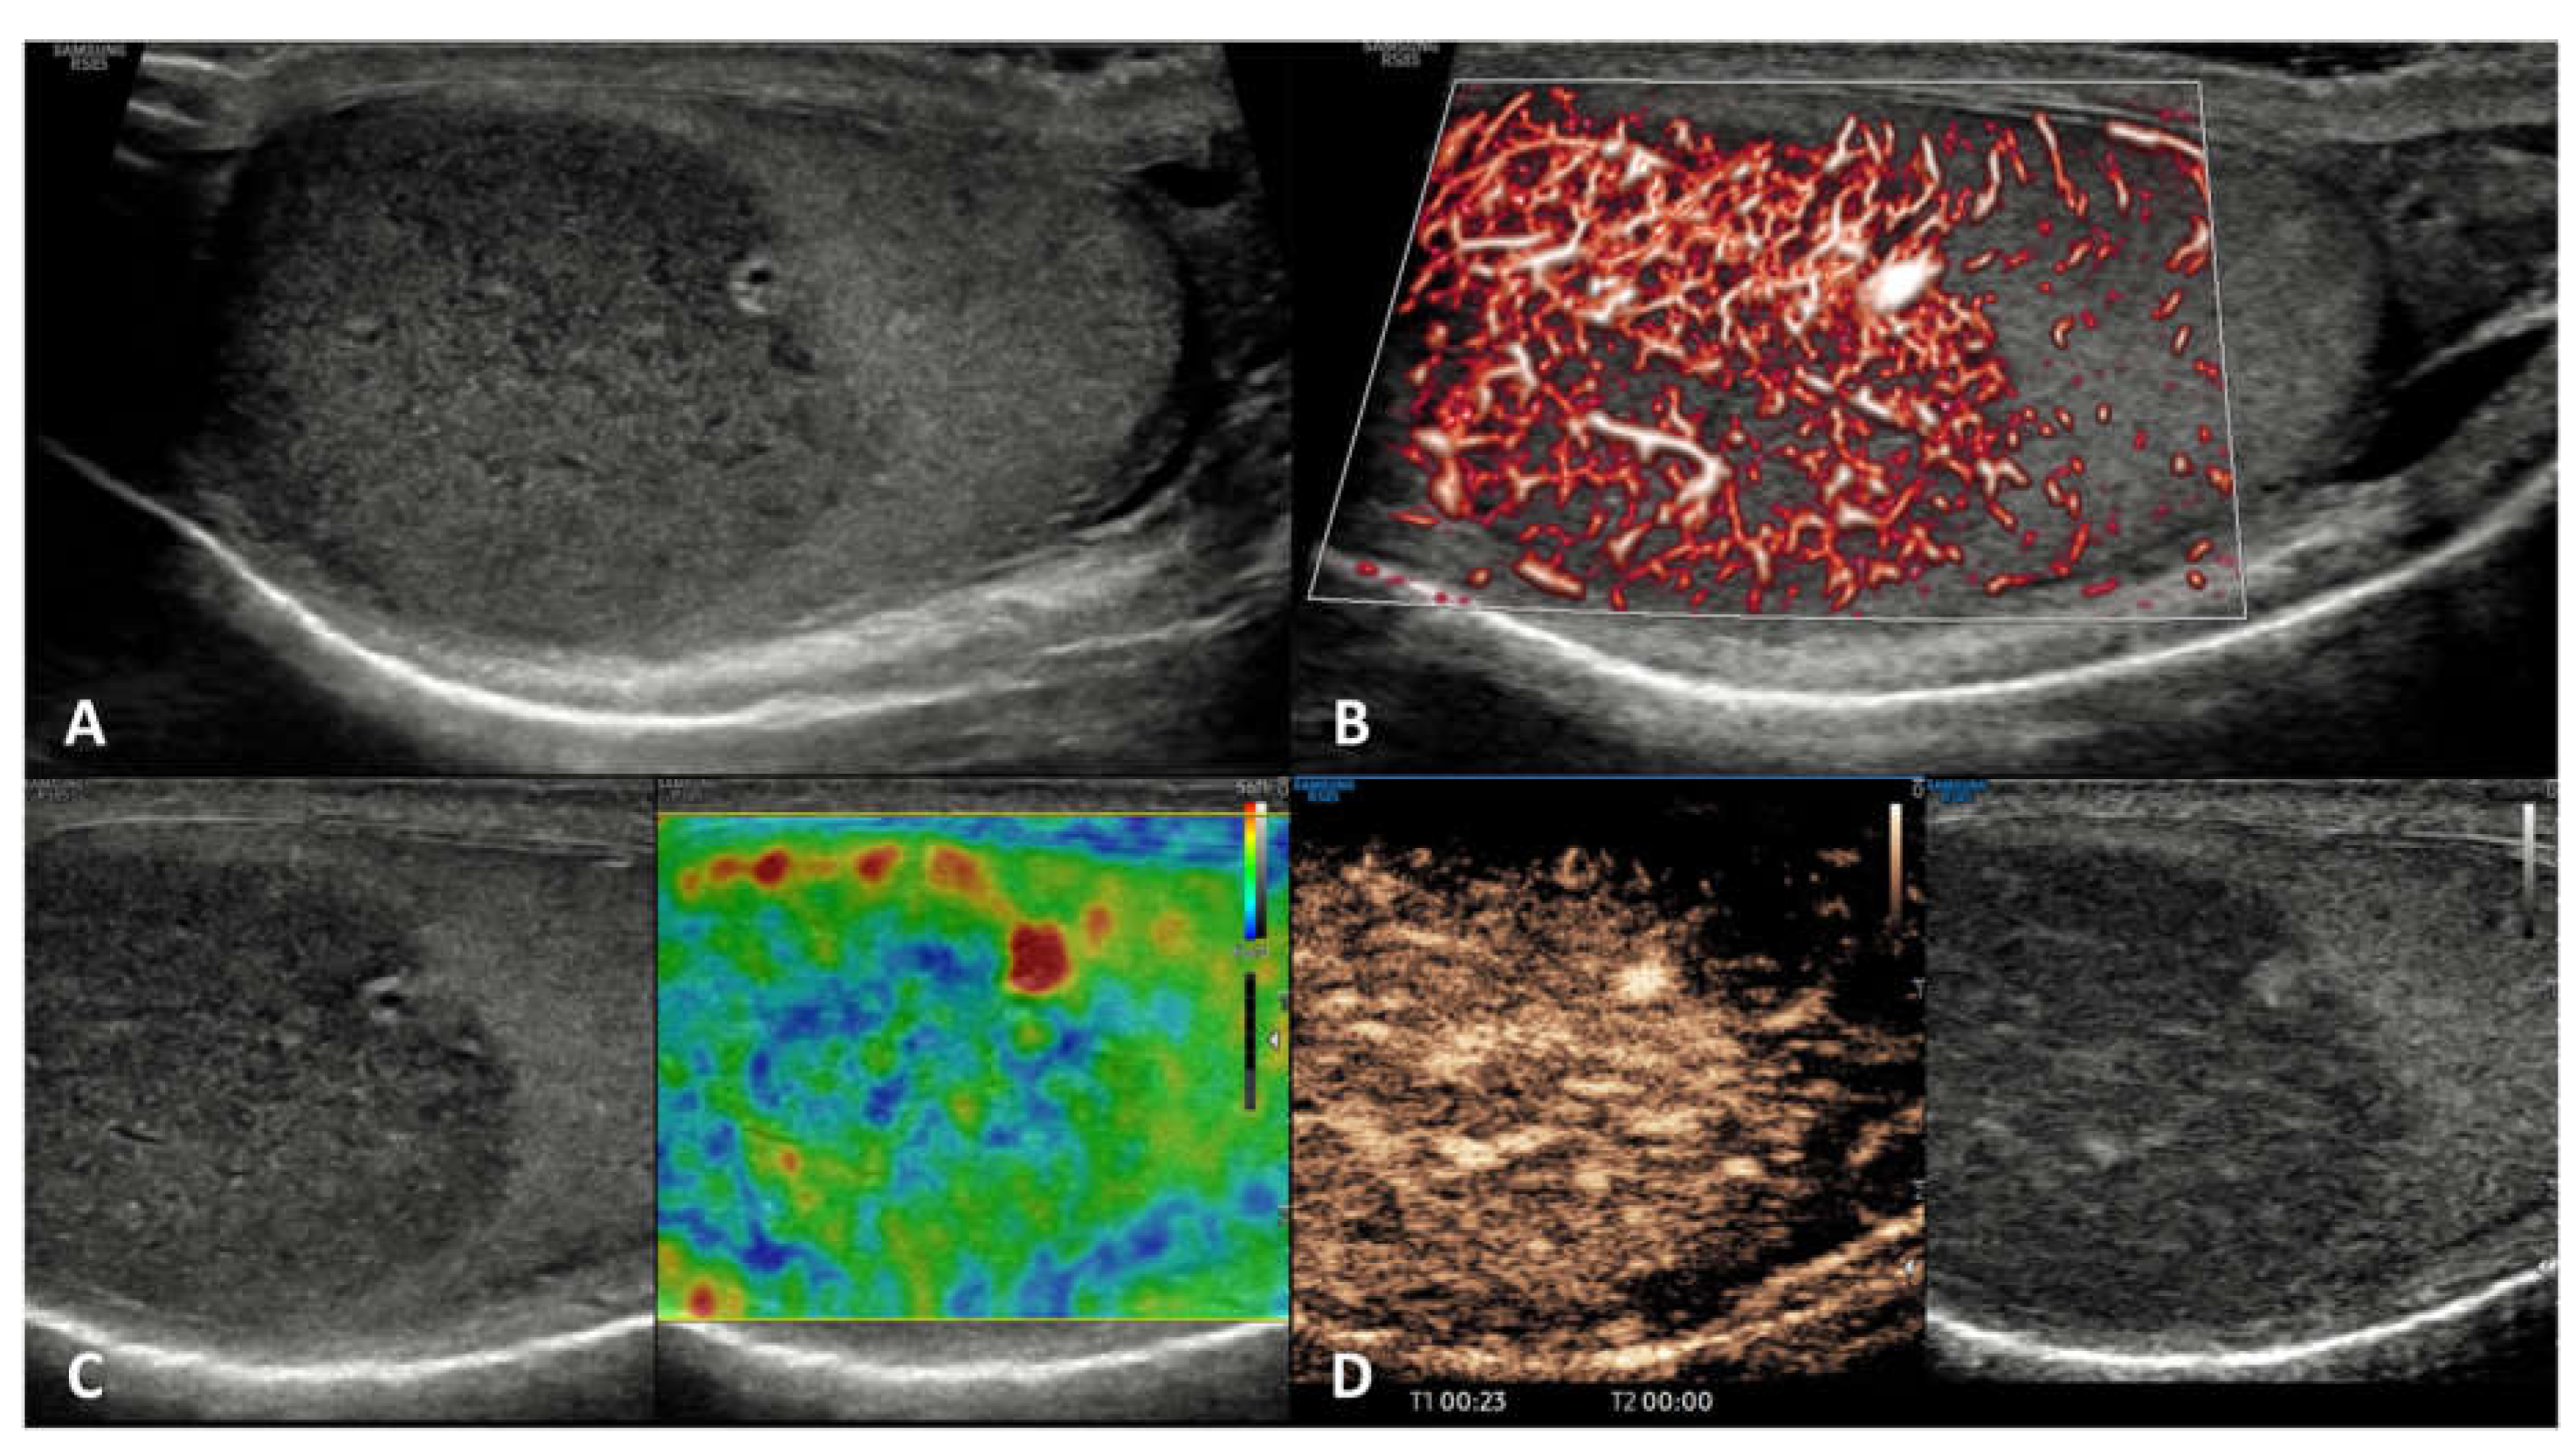

6.1. Seminomatous TGCTs (s-TGCTs)

Hypoechoic homogeneous round or oval lesion, occasionally multinodular or with polycyclic lobulated margins (unfrequently inhomogeneous) |

Hypervascularized, with arborization and branches | Homogeneously hyperenhanced (rapid wash-in and wash-out) |

Hard lesions with low/absent elastic strain |